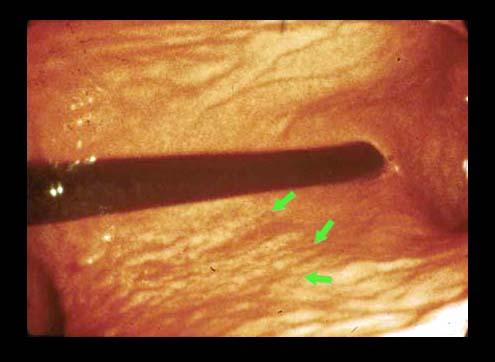

clasificación del pacienteTumor Maligno del Sistema Linfático/Linfoma Maligno

parte(separada por órganos)estómago(región)/cuerpo

método de exámenEndoscopia

clasificación ectoscópica de tumoresTipo 0(tipo superficial)/Tipo IIb(IIb+IIa)

diámetro mayor del tumor40 -

grado de penetraciónsm